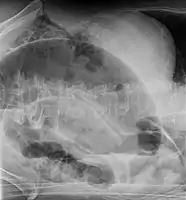

After taking a thorough history, the diagnosis of colonic volvulus is usually easily included in the differential diagnosis. Abdominal plain x-rays are commonly confirmatory for a volvulus, especially if a "bent inner tube" sign or a "coffee bean" sign are seen. These refer to the shape of the air filled closed loop of colon which forms the volvulus. Should the diagnosis be in doubt, a barium enema may be used to demonstrate a "bird's beak" at the point where the segment of proximal bowel and distal bowel rotate to form the volvulus.

This area shows an acute and sharp tapering and looks like a bird's beak. If a perforation is suspected, barium should not be used due to its potentially lethal effects when distributed throughout the free infraperitoneal cavity. Gastrografin, which is safer, can be substituted for barium.